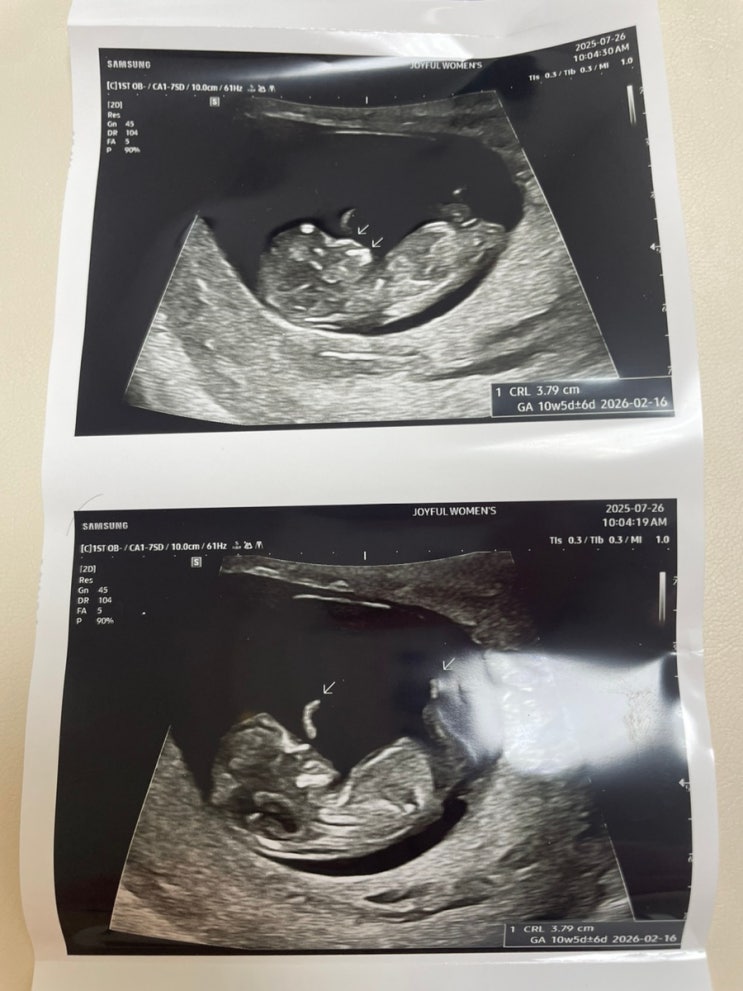

임신 10주1일차 초음파 (경산모)

임신 10주 1일차 오랜만에 올리는 초음파 사진이에요 :) 둘찌 ㅋㅋ 임신 10주 1일차에요. 첫째 육아로 정신...